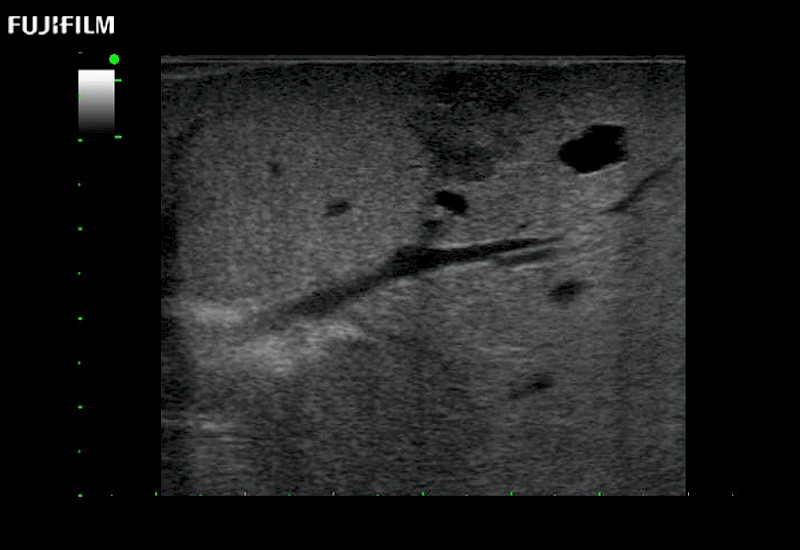

Curved array deep penetration “T” style finger-grip transducer for open surgical procedures.